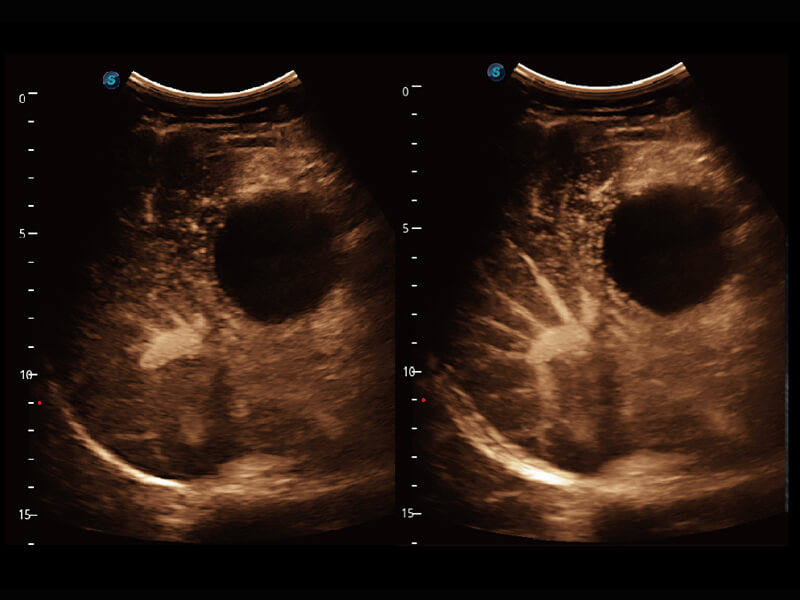

成像功能

S60探头工艺,从前端信号处理每一个环节采集无损声学数据,真实还原组织原貌,再现解剖细节。